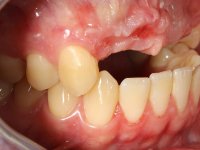

Male patient, 22 years old, non-smoker, appear in our dental office 6 months after a car accident where he lost teeth 21, 22, 23 and 24. Teeth 12 and 11 present mobility grade III, thus with a prognosis of extraction. The gengiva architecture of the edentulous area presents a recession and a flat surface.

10 weeks after the surgery, a first impression was done to do a CAD-CAM provisional bridge (based on the diagnostic wax-up), that worked the soft tissue architecture during two months. This architecture was copied in a second impression by individualizing the impression copings in their emerging profile.

The working model was scanned and the dental technician developed a zirconia framework based on the diagnostic wax-up. This framework try-in was done, the perfect fit was assessed, and a final impression was done with a light silicone.